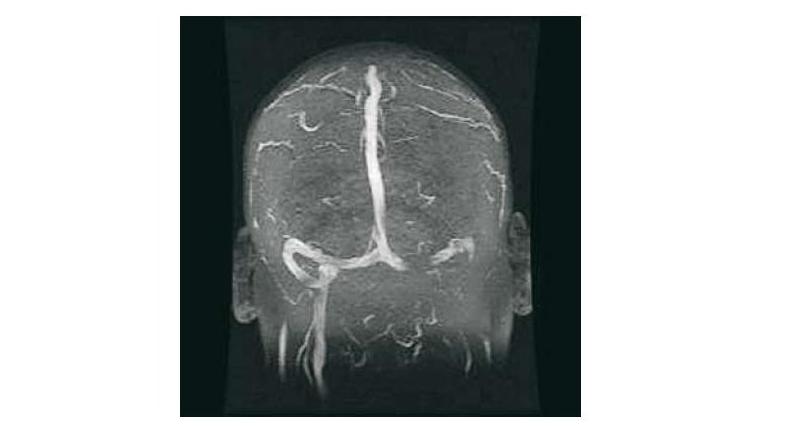

Nueva guía para el diagnóstico y tratamiento de la trombosis venosa cerebral

19 septiembre 2017